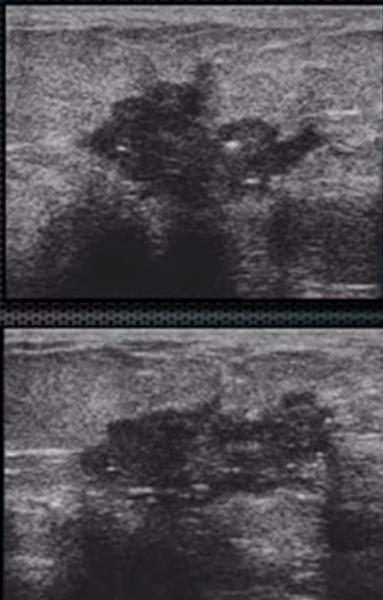

What is a Complex Cysts?

benign breast condition

contain some low level internal echotexture or intra-cystic debris.

Risk of malignancy among complicated breast cysts is thought to be 0.3-2%

What is the Sonographic Appearance of Complex Cysts?

Low to medium echogenicity

Irregular walls

hetertogenous

fluid filled levels

septations

wall thickening

debris

varying degrees of shadowing

What are the presentations of Complex Cysts?

What is Abscess?

benign breast condition

complication of mastitis, usually in subareolar region

What is the Sonographic Appearance of Abscess?

hyperechoic

Complex

Irregular borders

Posterior enhancement

Skin thickening

Increased color flow